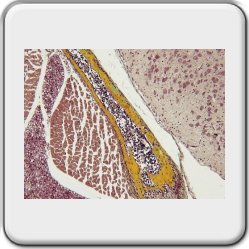

De getoonde preparaatfoto's tonen de kleurenpracht van de MOVAT kleuring.